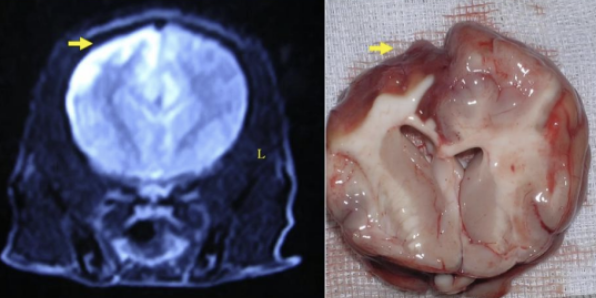

![]() GME case | - ์ผ์ชฝ ๋์ ์ ๋ฐ์ ์ผ๋ก ์ฌํ ์ผ์ฆ ์๊ฒฌ - autopsy ๊ฒฐ๊ณผ, cerebral parenchyma์ swelling - ๋น๋์นญ์ ์ธ ์ธก๋์ค ๊ด์ฐฐ๋จ |

![]() NME (YT) | - T1 image์์๋ hyposignal (์ด๋ก๊ฒ ๋ณด์) - T2 image์์๋ hypersignal (๋ฐ๊ฒ ๋ณด์) โ NME ์ ํน์ง! * GME๋ T1์์ isoignal, T2์์ hypersignal |

![]() NME case | - ์ค๋ฅธ์ชฝ ๋์ temporal ์์ญ์ ๋ง์ ์ผ์ฆ ํ์ธ - ๋ถ๊ฒ ๊ฒฐ๊ณผ gray matter ์ผ๋ถ๊ฐ ์์ ํ ๊ดด์ฌ๋ ๊ฒ์ ํ์ธ |